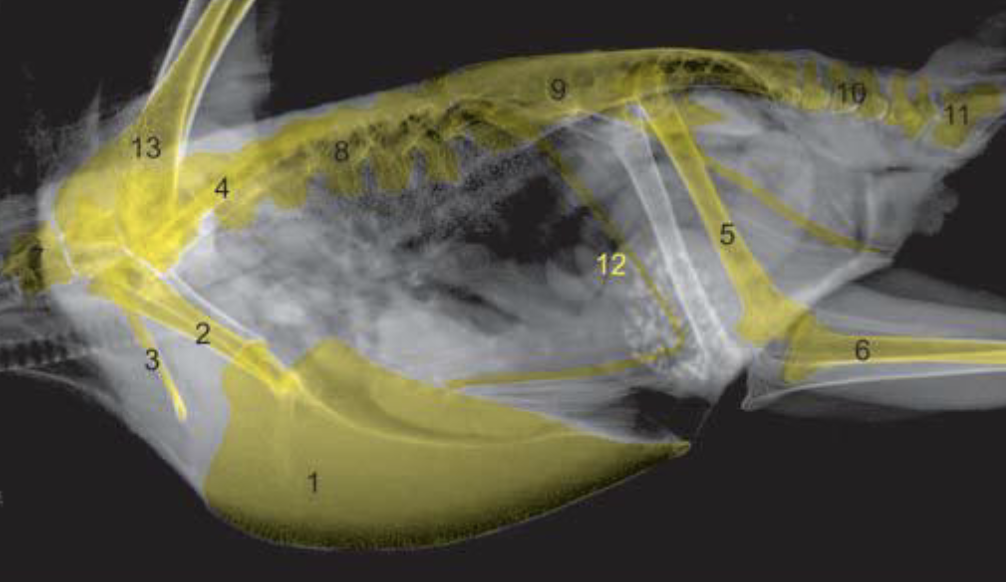

What are the anatomical structures labelled in this image?

A

7: tibiotarsus

1: humerus

3: clavicle

2: coracoid

11: pygostyle

6: femur

4: scapula

8: fibula

What are the characteristics of the lateral view in birds?

-typically a right lateral view

-coxofemoral joints and shoulder joints will be superimposed

What are the anatomic structures labelled in this image?

7/8/10/11: vertebrae

5: femur

1: sternum/keel

9: synsacrum

6: tibiotarsus